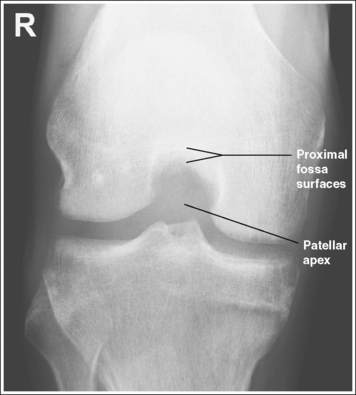

The knee demonstrates an AP projection. The medial and lateral femoral epicondyles are in profile, the femoral condyles are symmetrical, the intercondylar eminence is centered within the intercondylar fossa, and the tibia is superimposed over 0.25 inch (0.6 cm) of the fibular head.

• Effect of rotation. If the femoral epicondyles are not positioned parallel with the IR, an AP projection has not been obtained. If the patient's leg was not internally rotated enough to place the epicondyles at equal distances from the IR, they are not in profile, the medial femoral condyle appears larger than the lateral condyle, and the tibia is superimposed over more than 0.25 inch (0.6 cm) of the fibular head (see Image 54). If the patient's leg was internally rotated more than needed to place the femoral epicondyles at equal distances from the IR, the epicondyles are not demonstrated in profile, the lateral femoral condyle appears larger than the medial condyle, and the tibia is superimposed over less than 0.25 inch (0.6 cm) of the fibular head (see Image 55).

• Center the central ray to the midline of the knee at a level 1 inch (2.5 cm) distal to the palpable medial epicondyle to place the knee joint in the center of the exposure field. (As long as the knee remains extended, an alternative central ray placement is 0.5 inch (1.25 cm) distal to the patellar apex.) Open the longitudinal collimation enough to include one fourth of the distal femur and proximal lower leg. Transverse collimation should be to within 0.5 inch (1.25 cm) of the knee skin line.